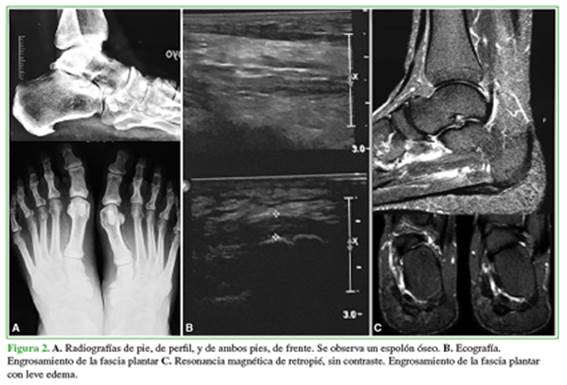

En general, no se requieren demasiados estudios complementarios para su diagnóstico, las radiografías simples pueden mostrar calcificaciones crónicas en la inserción de la fascia plantar o eventualmente trastornos del apoyo asociados, como pie plano o cavo varo; la ecografía y la resonancia magnética confirman el diagnóstico al mostrar la inflamación, la degeneración o el engrosamiento de la fascia plantar y son útiles también para evaluar situaciones agregadas o descartar otras causas de dolor de talón (Figura 2).